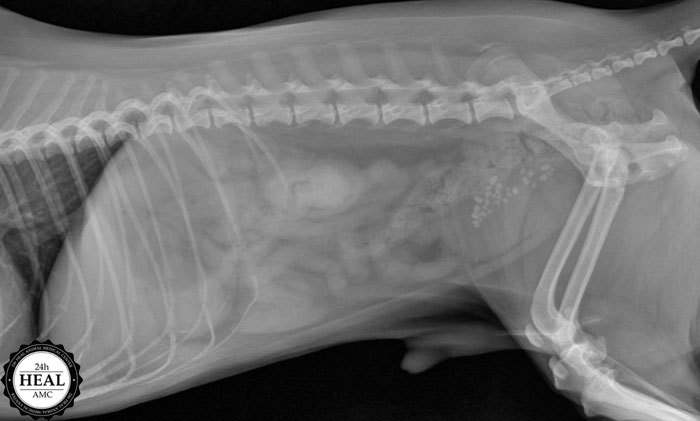

수술을 하기 전에는 반드시 상태 확인을 위한 초음파와 엑스레이 검사를 하는데

엑스레이를 찍어보니 오른쪽 상복부에 이물질이 있음을 확인한 이물질 소견이 있었습니다.

이렇게 이물질이 있는 경우 엑스레이 촬영과 초음파 검사로 진단할 수 있습니다.

이물질이 우측 신장 위와 위장 아래에 위치하고 있음을 확인할 수 있으며,

이물질의 크기는 2~3cm 정도의 크기였습니다.

이물질 감별을 위한 x선 검사와 초음파 검사를 진행하던 중 방광 측에도 결석 소견이 함께 발견되어

결론적으로 장내 이물질과 방광결석으로 진단하였습니다.

이물질이 위에 없고 현재는 장으로 전달된 상태에서 마취 전 검사도 함께 하고,